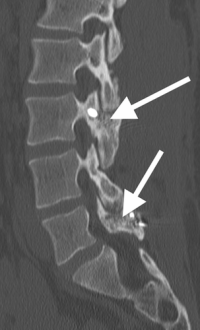

(Click to Enlarge Image) X-ray of pars repair. Note the screw through one side of pars and thewire tightening the other side.